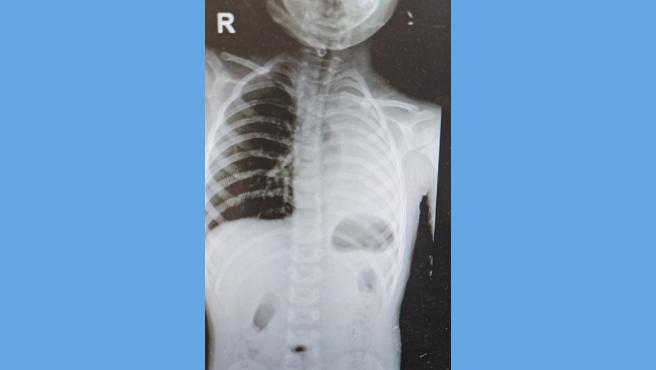

Profesionales de la salud del Hospital de Emergencias Pediátricas (HEP) del Minsa realizaron con éxito una broncoscopía a un niño de 3 años y 2